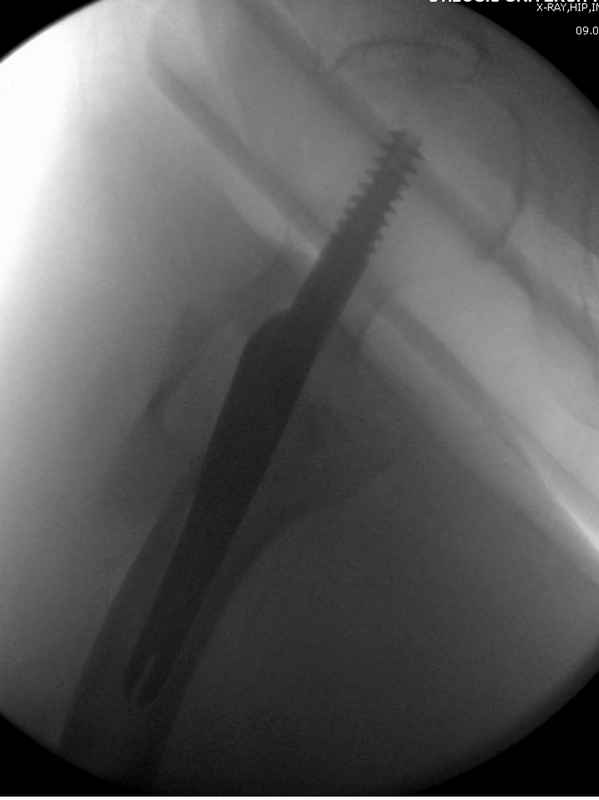

Здесь пара случаев фиксации похожих переломов:

первый высокоэнергетическая травма 36 лет